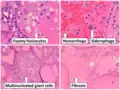

Thyroid hyperplasia with a Sanderson polster, which is a group of small follicles that protrude into the lumen of a larger follicle. It should not be confused for papillary projections. Various forms of degeneration are typically seen, with various forms pictured.

Various forms of degeneration are typically seen, with various forms pictured.